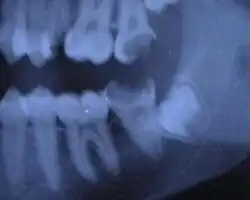

Die folgenden Röntgenbilder sind Ausschnitte aus Orthopantomogrammen (OPG):

-

Weisheitszahn 38; retiniert und verlagert; mesiale Kippung um fast 90°

Weisheitszahn 38; fast bis zur Kauebene durchgebrochen; distale Wand vollständig im Knochen; voll ausgebildete Wurzel; Wurzelspitzen projizieren sich auf den Nervus alveolaris inferior

Weisheitszahn 38; retiniert und verlagert – stark nach mesial gekippt; sehr kurze Wurzelspitzen projizieren sich auf den Nervus alveolaris inferior